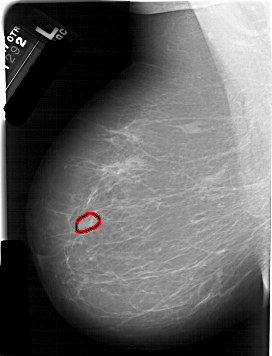

A_1128_1.RIGHT_MLO

FILE: A_1128_1.RIGHT_MLO.OVERLAY

TOTAL_ABNORMALITIES 1

ABNORMALITY 1

LESION_TYPE MASS SHAPE LOBULATED MARGINS MICROLOBULATED

ASSESSMENT 4

SUBTLETY 5

PATHOLOGY MALIGNANT

TOTAL_OUTLINES 1

BOUNDARY